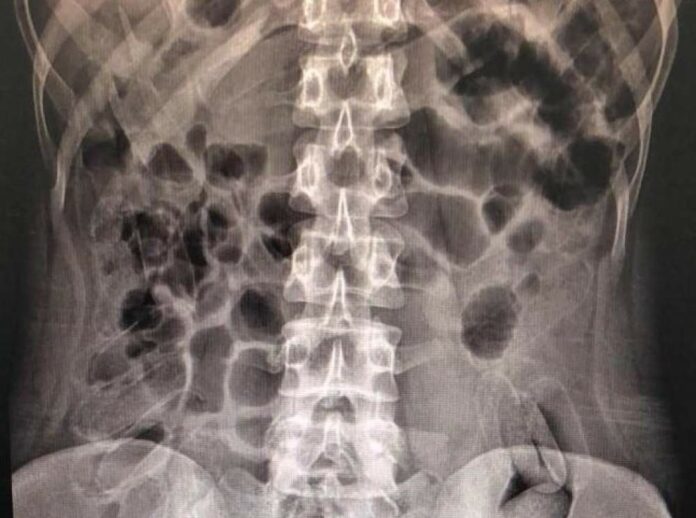

Cinco pessoas foram levadas à Santa Casa de Araçatuba (SP) pela Polícia Rodoviária Federal na manhã desta quinta-feira (23) para atendimento médico, sob suspeita de tráfico de drogas. Segundo a assessoria do hospital, quatro delas expeliram cápsulas de cocaína, enquanto exames confirmaram que o quinto suspeito não havia ingerido o entorpecente.

Os pacientes, três mulheres e um homem, relataram ter engolido entre 30 e 50 cápsulas da droga. Até o final da manhã, cerca de 50% do total já havia sido expelido. Todos os procedimentos médicos estão sendo acompanhados por policiais rodoviários, e o estado de saúde dos pacientes é considerado estável.